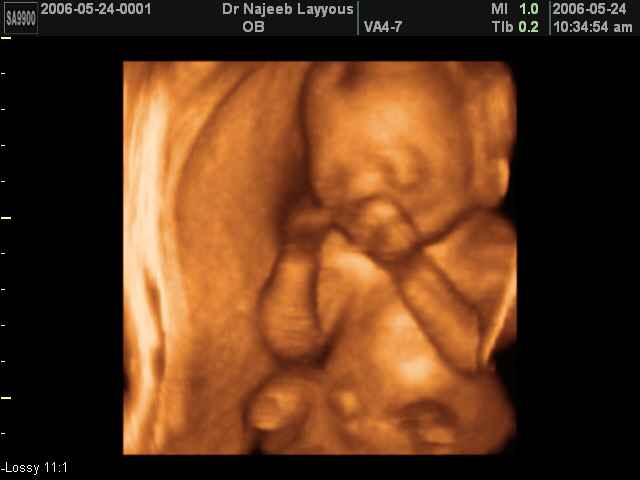

- صور لتصرفات الجنين داخل الرحم

صور لتصرفات الجنين داخل الرحم بجهاز الالتراساوند ثلاثي الأبعاد | الدكتور نجيب ليوس